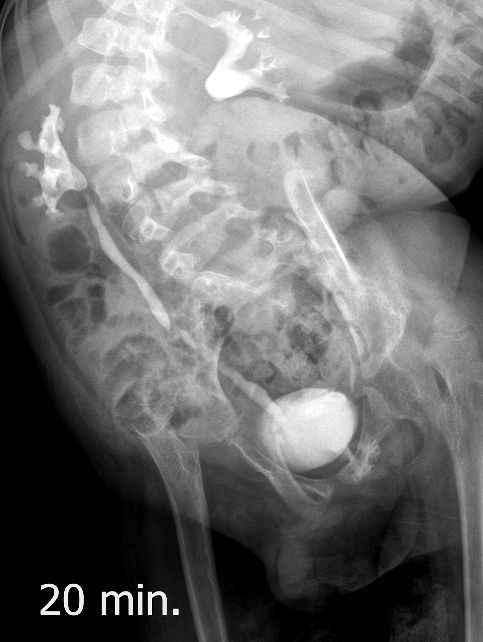

Поскольку откликов нет, добавляю экскреторные урограммы этого же пациента

Нейрогенный мочевой пузырь (?), МКБ, конкремент мочевого пузыря, двухсторонний мегауретер, конкремент правой почки.

И что законтрастировалось на экскреторных урограммах около мочевого пузыря?

DX0004.jpg

Стриктура уретры с расширением ее проксимального отдела?

Если честно, и я изначально не совсем понял, где находится конкремент (а это конечно же конкремент), локализованный на урограммах. При первичном исследовании на УЗИ его я не видел (либо он спрятался за тенью конкремента мочевого пузыря, либо я обрадовался редкой находке конкремента такого размера в мочевом пузыре - 2.5 см, и не посмотрел что ниже). Тем не менее при ретроспективном анализе архивированных сонограмм, как мне кажется, он попал в один из сканов, м.б. не совсем чётко.

И всё -же, где конкремент :?:

Возможно, в дивертикуле либо в нижней трети мочеточника..

Верификация:

Выдержка из протокола операции- "...вскрыт мочевой пузырь, обнаружен камень 4 х 3х 2.5 см, плотный, удалён. При дальнейшей ревизии мочевого пузыря обнаружен вколоченный камень в шейке мочевого пузыря и в уретре, удалён камень 2 х 1.5 х 1.5 см. При осмотре устья левого мочеточника - последний зияет, мочеточник расширен до 1 см, учитывая расширение мочеточника, проведена антирефлюксная пластика по Грегуару..."

На экскреторной урограмме - размеры собирательной системы левой почки уменьшились. Визуализирована расшиенная контрастированная проксимальная уретра.